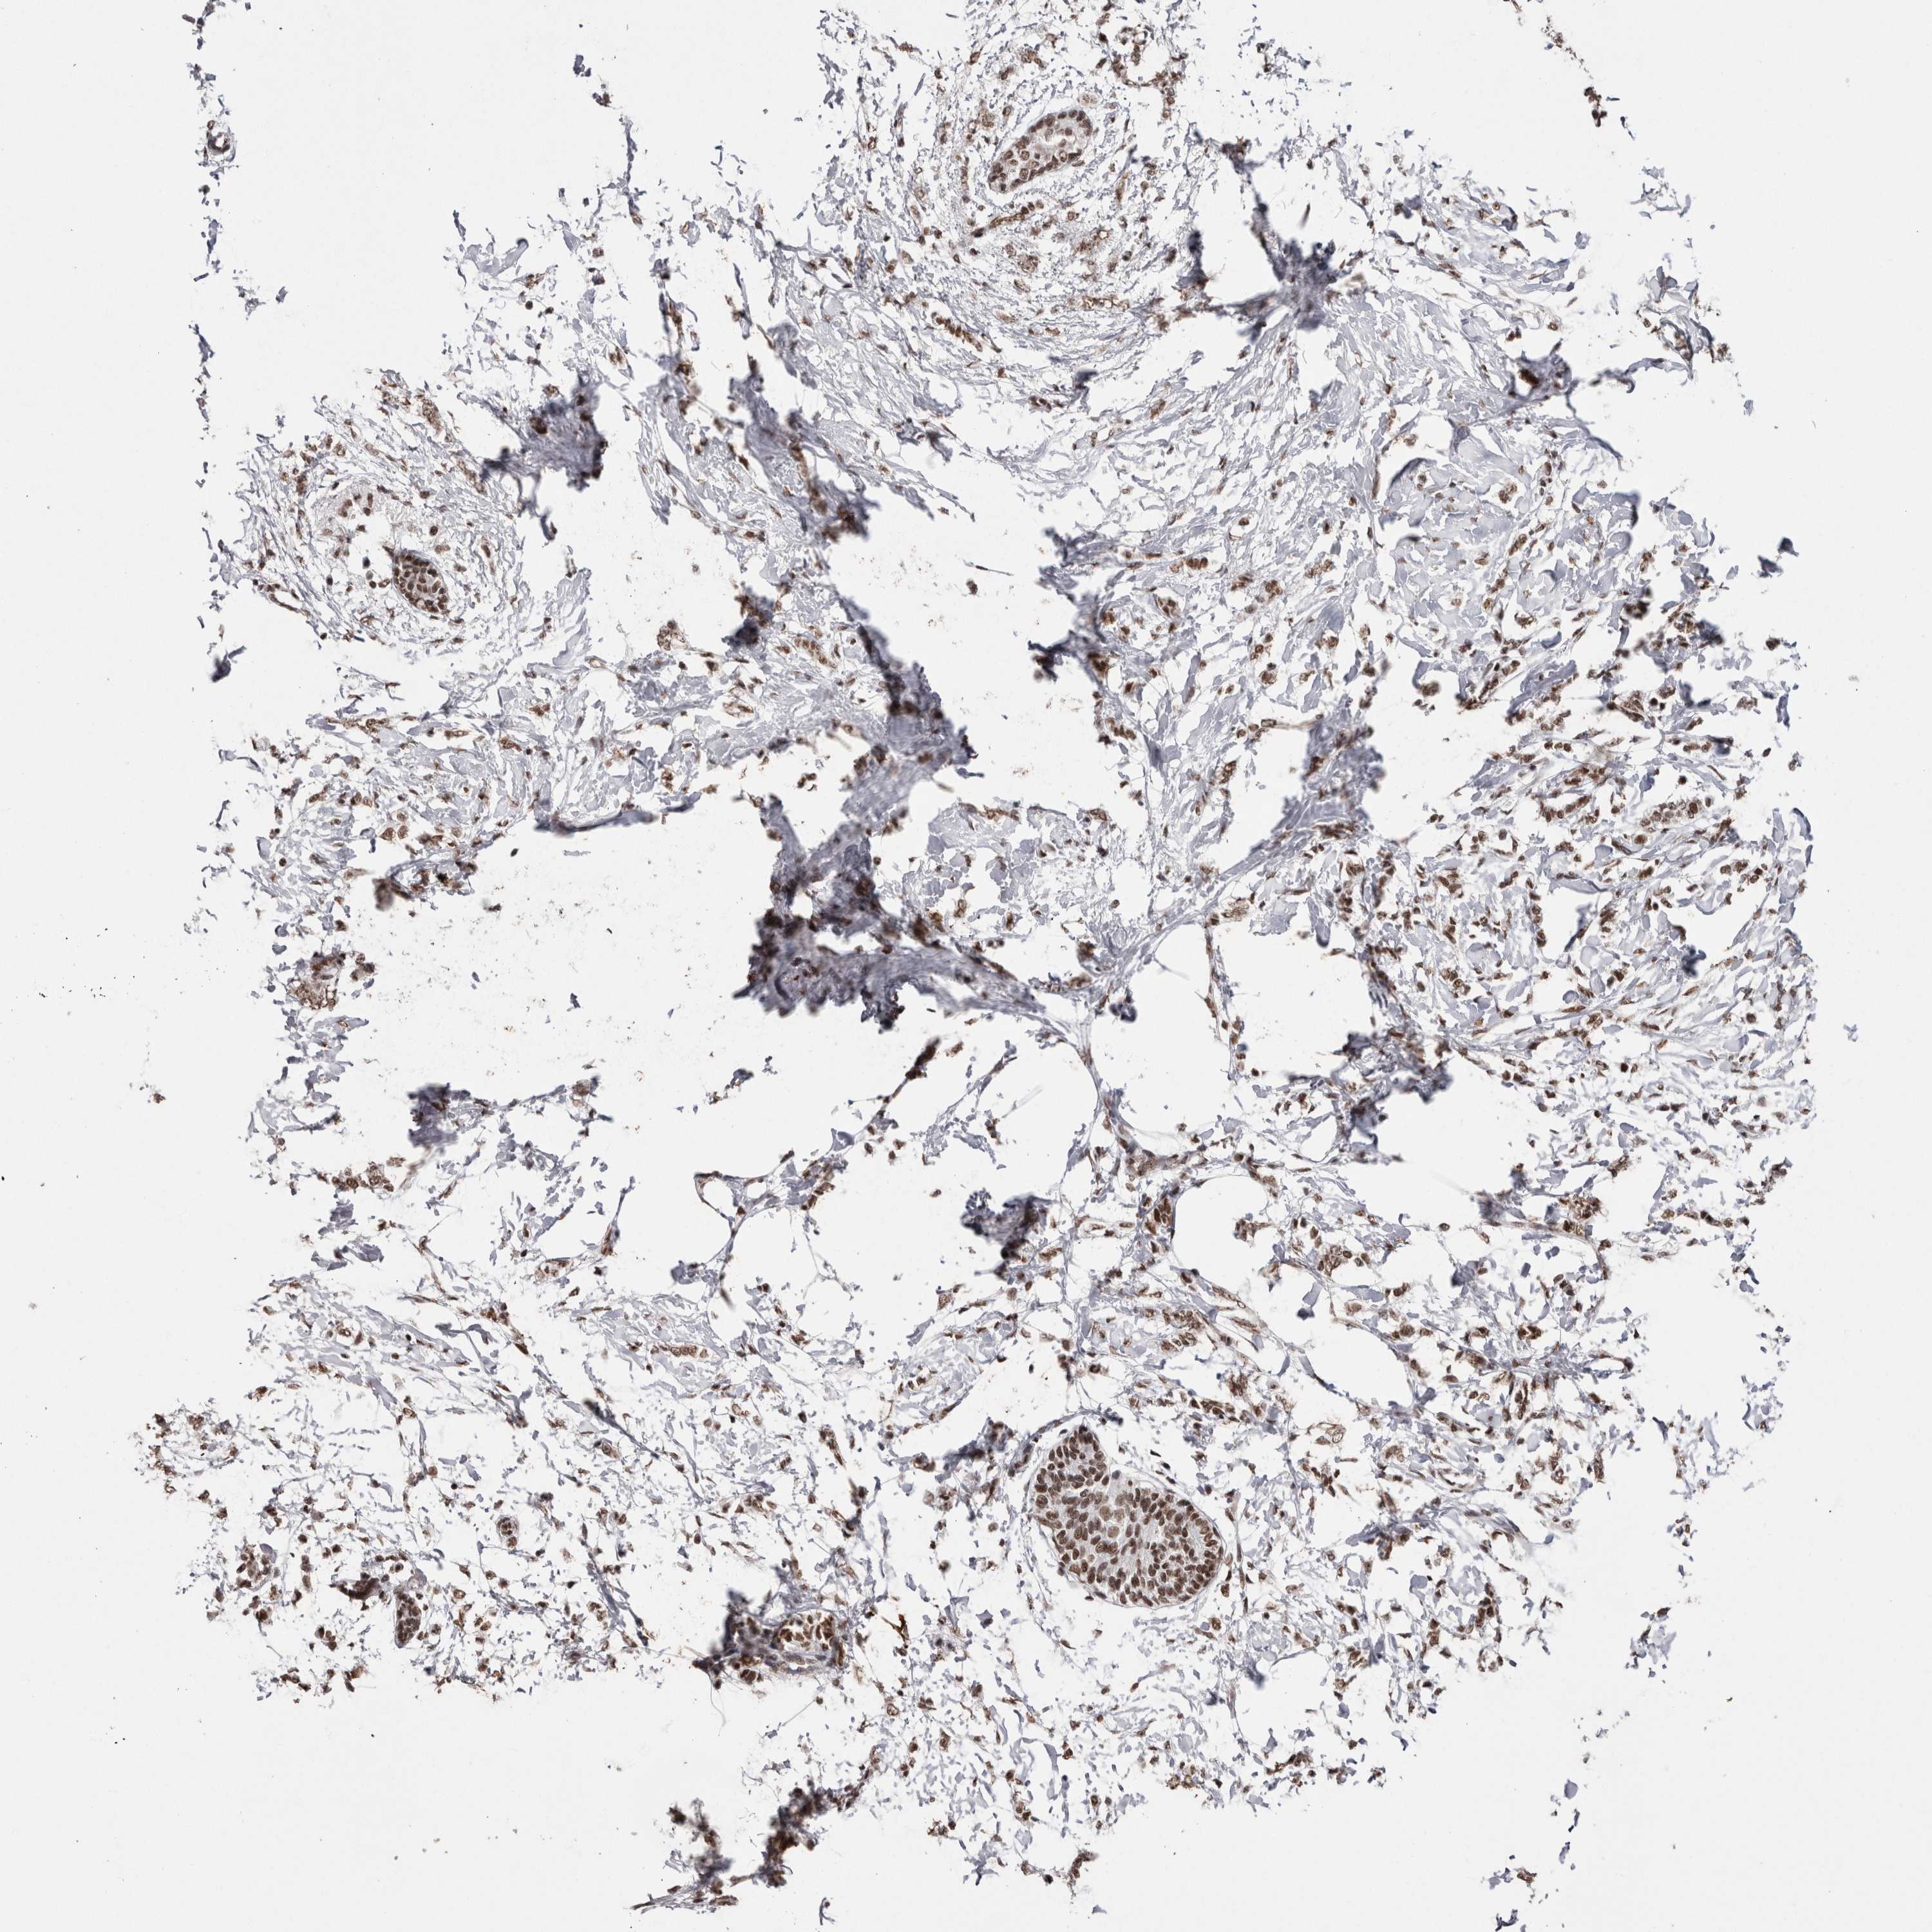

CANCER BREAST CANCER Show tissue menu

BRCA TCGA BRCA VALIDATION PROTEIN EXPRESSION